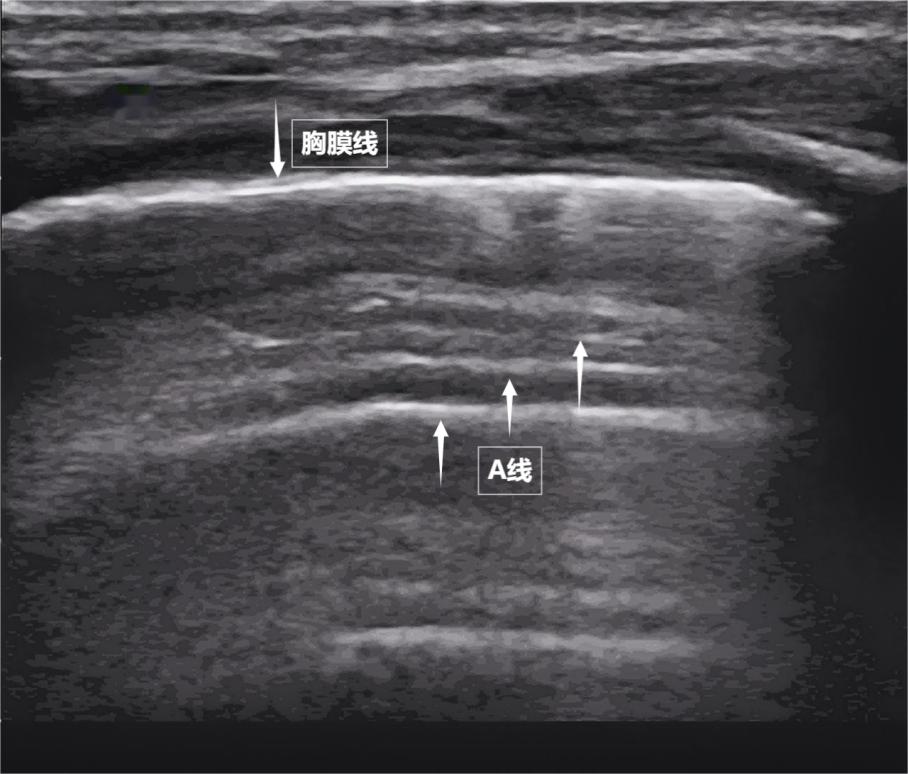

When the sound wave passes through the gaps between the ribs of the chest wall, it first encounters a smooth film closely attached to the surface of the lungs—the parietal pleura and visceral pleura. They are tightly adjacent to each other, with no excess gas or fluid in between. On the screen, they appear as a bright, smooth horizontal line, together forming the pleural line. This line is the "coastline" of the lungs. Below it, due to the strong reflection of sound waves by the large amount of gas in the alveoli, a series of bright, parallel lines appear on the screen, equally spaced and repeatedly appearing, extending continuously into the depth of the screen like waves—this is the A line (see the following image). The A line is a typical sign of a normally aerated lung. Its presence directly indicates that the lung surface is well-aerated and that there is no abnormal accumulation of fluid or gas in the pleural cavity.

Figure shows the ultrasound appearance of a normal newborn's lungs